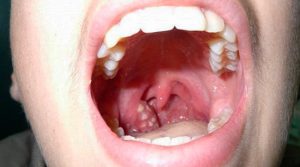

Amigdalite é a inflamação das amígdalas, aquelas “bolinhas” no fundo da garganta. Geralmente causada por vírus ou bactérias, ela traz dor, dificuldade para engolir e febre. Cuidados adequados aliviam os sintomas e evitam complicações. Saber reconhecer os sinais é o primeiro passo para cuidar da sua saúde.

Além da dor, febre é outro sintoma que bate forte. Geralmente, ela vem acompanhada de calafrios. Você pode notar também que suas amígdalas estão inchadas e vermelhas, às vezes com umas pintinhas brancas ou amareladas. O hálito ruim também é comum, porque as bactérias gostam de se instalar ali. E, se você puder se olhar no espelho, vai ver que elas estão bem maiores que o normal. É um sinal de alerta que seu corpo dá.

Quando a amigdalite aparece em crianças, é fundamental ficar de olho. Essa inflamação nas amígdalas, aquelas bolinhas de defesa que ficam lá no fundo da garganta, pode ter causas variadas, sendo as mais comuns as virais e as bacterianas. A febre alta é um sintoma clássico, junto com a dor de garganta que dificulta até a fala e a alimentação. Ver a garganta avermelhada e com placas brancas é um sinal que não passa despercebido.

| Identificando os Primeiros Sintomas da Amigdalite | Dor de garganta intensa, vermelhidão e inchaço nas amígdalas, dificuldade para engolir, febre, dor de cabeça, mal-estar geral. Às vezes, pontos brancos ou pus nas amígdalas. | Preste atenção a qualquer desconforto incomum na garganta. Verifique o espelho se possível para notar alterações visuais. |